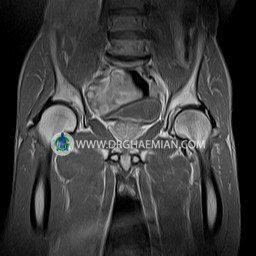

پزشکان اغلب از تصویربرداری ام آر آی برای تشخیص و درمان عارضه های پزشکی که فقط با استفاده از اشعه ایکس یا میدان مغناطیسی و امواج رادیویی قابل مشاهده است، استفاده می کنند. دستگاه ام آر آی تصاویر دقیق از ساختار های داخلی بدن ایجاد می کند. در این کیس استئومیلیت لگن، آتروز و سنیویت دیده می شود.

HIP JOINT MRI

( without contrast )

Technique : coronal STIR , coronal T2 , Axial T1 , axial T2 .

REPORT:

The femoral heads and acetabula are normal shape , signal intensity and the femoral heads are well covered by the acetabular margins .

The joint spaces are of normal width without fluid collection .

The articular surfaces are smooth and congruent and show normal cortical thickness .

Each femoral shaft has normal margins and contains a normal bone marrow signal .

The imaged muscles and the lesser pelvis show no abnormalities .

– Heterogeneous signal change (high T2/STIR , low T1) in proximal metaepiphysis of left femur without articular surface irregularity suggestive for bone bruise (stress fracture?), osteomyelitis & arthritis and marrow infiltration (less probable)

– Left hip joint effusion suggestive for synovitis

are seen.

COMMENT: Clinical correlation and MRI with contrast are recommended.